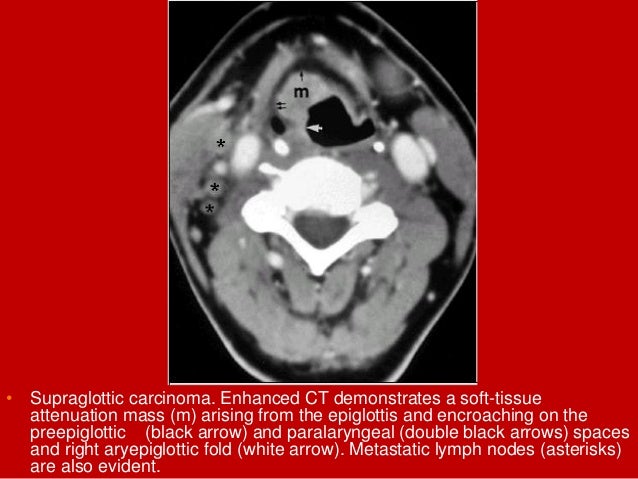

18. 18. • Supraglottic carcinoma. Enhanced CT demonstrates a soft-tissue attenuation mass (m) arising from the epiglottis and encroaching on the preepiglottic (black arrow) and paralaryngeal (double black arrows) spaces and right aryepiglottic fold (white arrow). Metastatic lymph nodes (asterisks) are also evident.